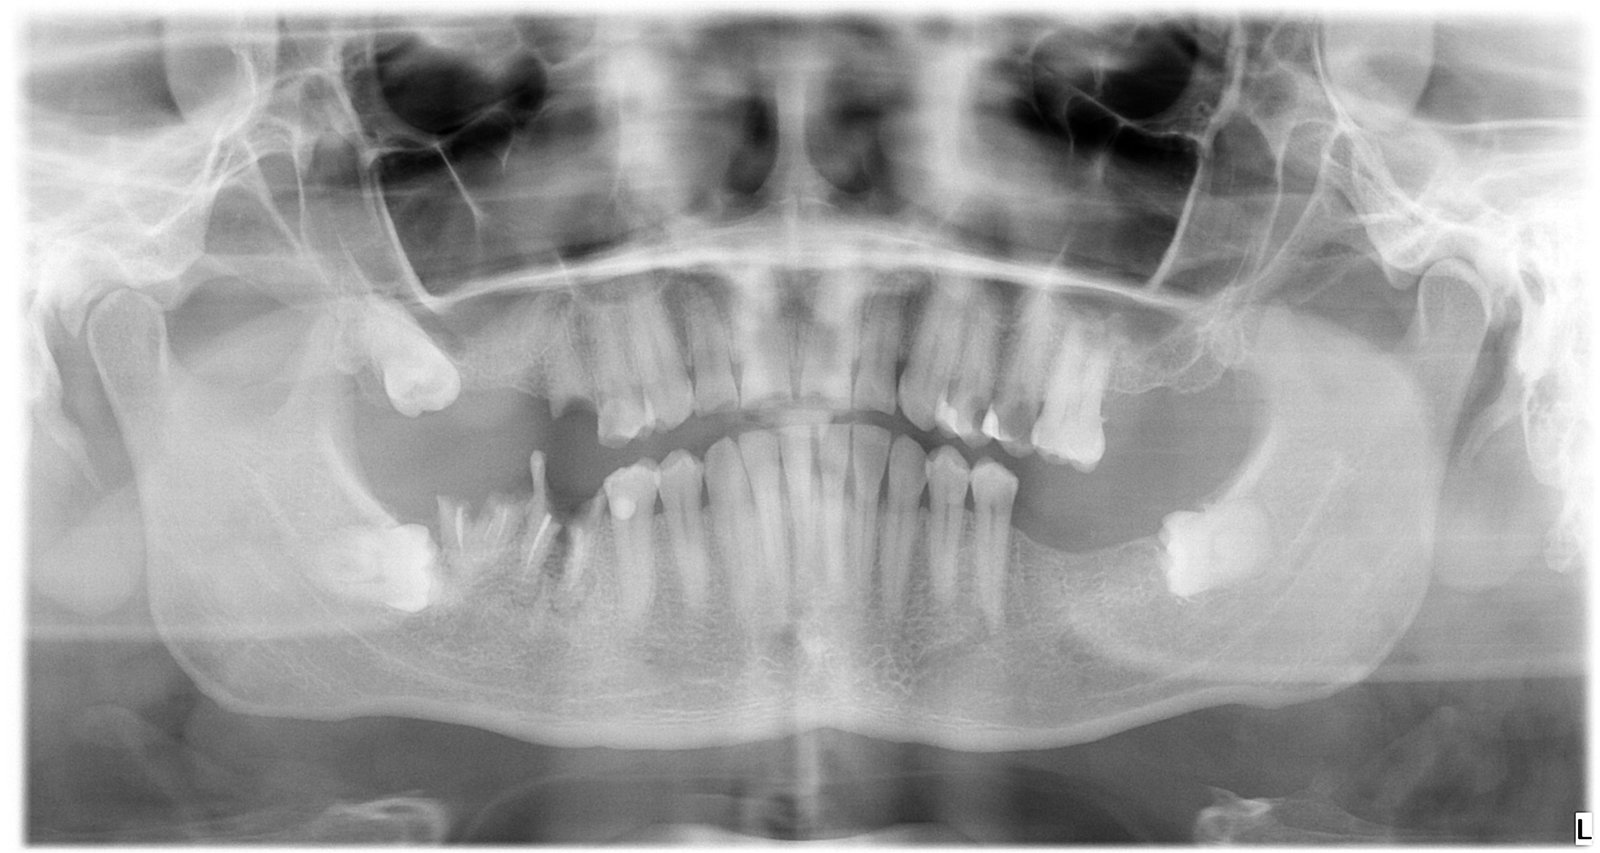

Caso 1 - caso de Carga inmediata

La paciente acudió con la necesidad de recuperar sus dientes de forma rápida y sin largos tiempos de espera. Gracias a la técnica de carga inmediata, colocamos dientes fijos el mismo día, devolviéndole su sonrisa de manera inmediata y segura.

Esta imagen muestra la planificación precisa del tratamiento de carga inmediata, clave para garantizar estabilidad desde el primer momento.